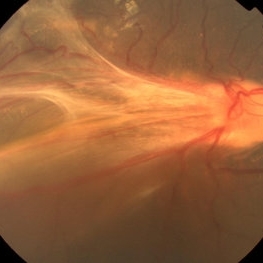

Fundus photograph of a 6-year-old boy with a falciform retinal detachment suspiciously associated with toxocariasis.

Photographer: Yusuke Takada, Osaka University Graduate School of Medicine